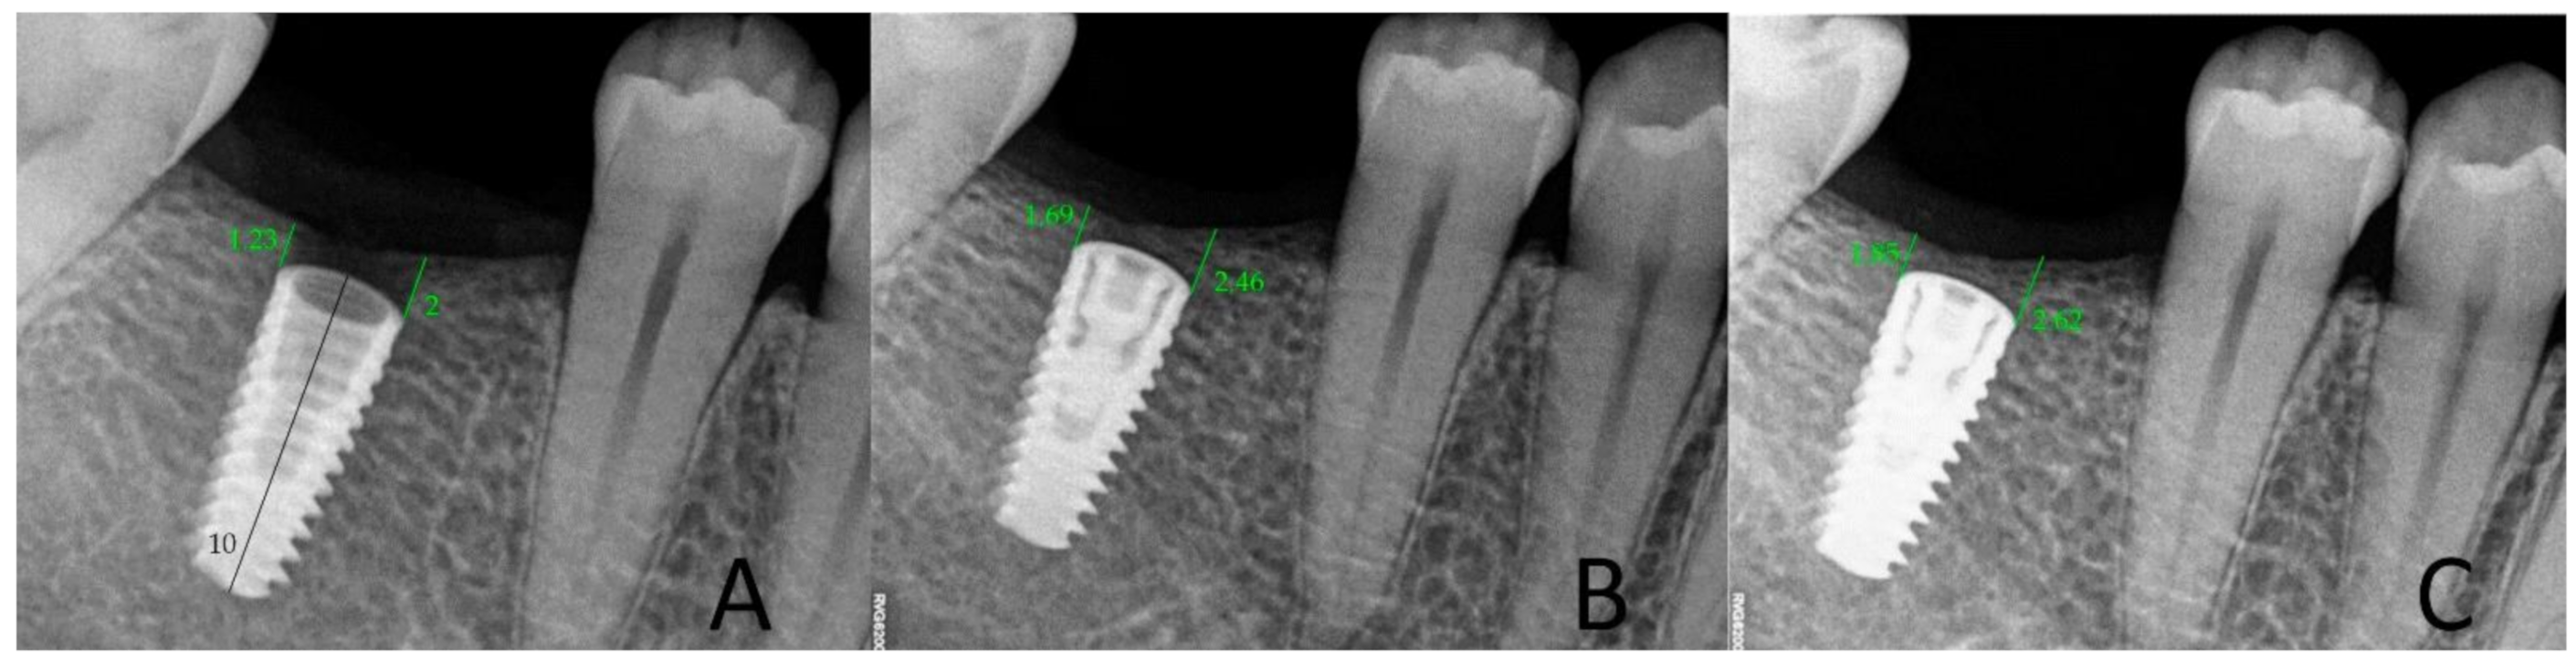

All control tests were performed by the second operator (GT). The evaluation of bone loss/growth was performed on the basis of radiovisiography (RVG) images taken with the long cone paralleling technique using a positioner (Figure 1). The bone level in the immediate proximity of the implant was determined using the RVG image analysis. Three targeted radiographic images were compared on the day of implantation, and after six and twelve weeks. Bone tissue loss or growth were assessed using software designed for analyzing digital radiovisiography. The calculated value was the arithmetical mean of the measurements performed on both sides of the implant that were visible in the two-dimensional image (the calculations were made starting at the head of the closing screw). To enable effective calibration, a measurement was made along the long axis of the implant (a) (Figure 2, Figure 3 and Figure 4), which was related to its actual length (y) and was calculated from Formula (1) as follows:

Figure 4.

Measurements of bone growth in the proximity of the implant (DIS, dental image software). (A) On the day of surgery; (B) after 6 weeks; (C) after 12 weeks, in study groups.